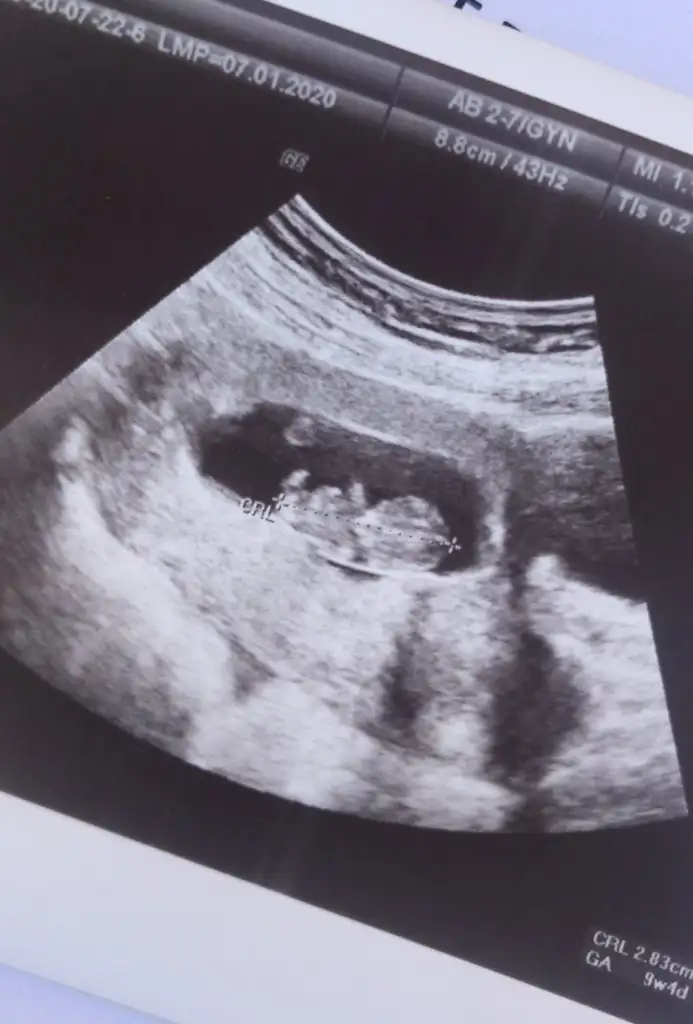

Nubu çok karanlık başka usg varmı erkek diyecem emin olamadımBenım ıcın de tahminde bulunur musunuz acaba 12+5 Haftadayım

Bunlar var ama gorunmuyo gıbı degil mıNubu çok karanlık başka usg varmı erkek diyecem emin olamadım

bi fotoğraf daha ekledim :)Ikra meyra merhaba abimin bebişi için tahmin alabilir miyiiim 12+4 benim ve arkadaşım için yaptıgınız tahmin doğru çıkmıştı bu arada